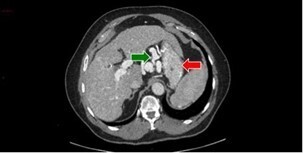

Question 3 - Dans les coupes précédentes, quelles sont les structures désignées par les flèches ?

Veine cave inférieure.

Corps vertébral.

Voies veineuses de dérivation péri-gastriques.

Flèche verte.